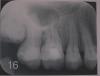

nikita10007 Опубликовано 6 мая, 2011 Поделиться Опубликовано 6 мая, 2011 (изменено) Рекомендовали удалить верхние шестерки и семерки. Неужели это необходимо? Буду признательна за ваши советы. Что делать и в каком порядке по срочности? Изменено 6 мая, 2011 пользователем nikita10007 Ссылка на комментарий

juli63 Опубликовано 10 мая, 2011 Поделиться Опубликовано 10 мая, 2011 вас беспокоят эти зубы на данный момент? 8(зубы мудрости)-совсем не нравятся, хоть и не прорезались. похоже проблемы с пародонтом. нужно перелечивать каналы в этих зубах и на нижней челюсти тоже Ссылка на комментарий

Bier Опубликовано 10 мая, 2011 Поделиться Опубликовано 10 мая, 2011 Это я на консультации предложил удалить эти зубы доктора, а вас не смущает карман до апексов у 26,27 ??? На мой взгляд однозначное удаление. что касается 16,17 - пациентке было сказано, что лечение возможно, но без гарантии, а стоимость его сопоставима или выше, чем имплантация. Др.Албан - как лечение каналов 26,27 повлияет на пародонтологическую картину в данной ситуации? Ссылка на комментарий

juli63 Опубликовано 10 мая, 2011 Поделиться Опубликовано 10 мая, 2011 Вы держали пациента в руках , Вам виднее. честно говоря, долго см на на обл. 26-27 и понадеялась, что это качество снимка не очень ... если карман до апекса-это явно не жилец. тут не то что "без гарантий", а "полный абзац". Ссылка на комментарий